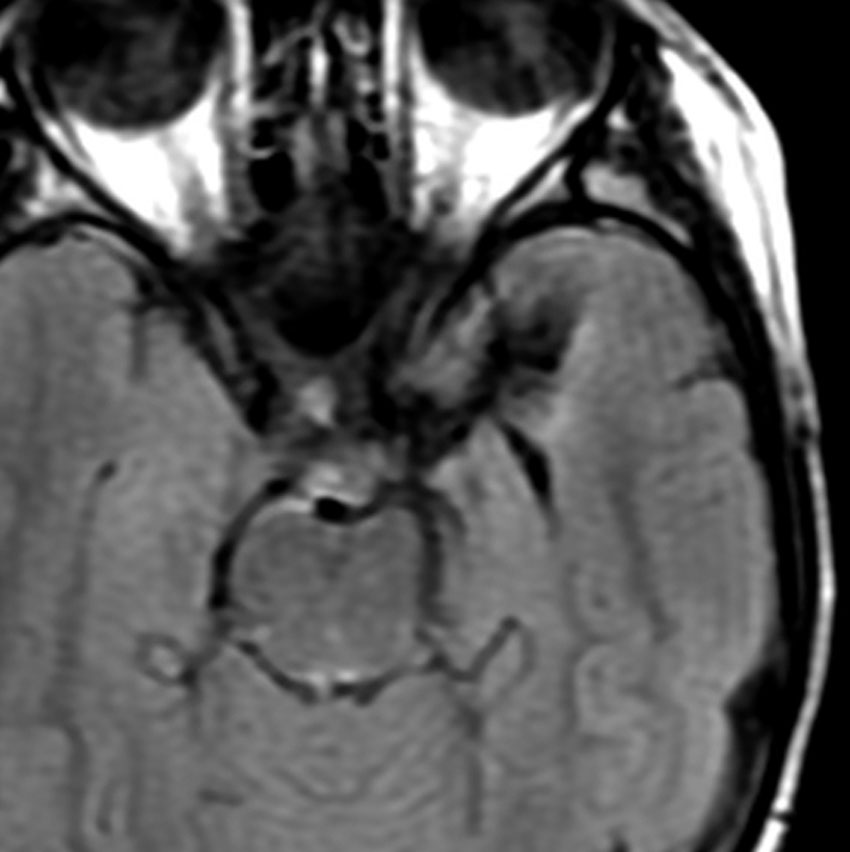

若い成人です,認知機能障害で発症しました。この画像を見るからに悪性神経膠腫,少なくともグレード3のグリオーマであることは明白です。しかし,グレード4膠芽腫あるいはグレード3退形成性星細胞腫にしては腫瘍周辺浮腫が軽すぎます。ですから,グレード3の退形成性乏突起膠腫 AO かも。認知機能の回復と温存を考量して,脳梁損傷と前交連損傷を避けて,右上前頭回と帯状回腫瘍を摘出しました。

左は術後のT1強調ガドリニウム増強像で,残存腫瘍がわかります。この腫瘍に対してICE (IFO/CDDP/VP-16) 化学療法を1コースしました。右側のMRIが1ヶ月後の画像です。このように1p/19q欠失のある退形成性乏突起膠腫は,化学療法感受性がとても高い悪性グリオーマです。ですから,手術で後遺症を残さないように,勢い込んで腫瘍を摘出しようとしないことが大切です。光顕診断はAOで,後々の解析で1p/19q codeletion でした。